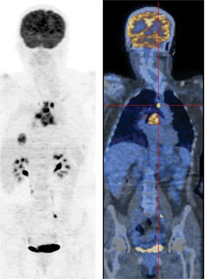

Oncology PET

The National Oncologic PET Registry (NOPR) was developed in response to the Centers for Medicare and Medicaid Services (CMS) proposal to expand coverage for FDG-PET to include cancers and indications not presently eligible for Medicare reimbursement.  This offers tremendous opportunity for demonstrating effective management of cancer patients and for the expansion of PET covered indications.

A PET scan with sodium fluoride F 18 injection (18F NaF) is a nuclear imaging test that scans your entire skeletal system and produces high-resolution images of your bones. These images are used to detect areas of abnormal bone growth associated with tumors.